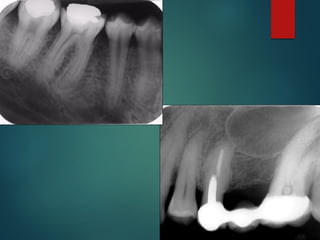

Clasificación Radiográfica

De Las Caries

 Incipiente de esmalte

 De esmalte

 Dentinaria superficial

 Dentinaria profunda

 Sobreproyectada en cámara pulpar

 Penetrante